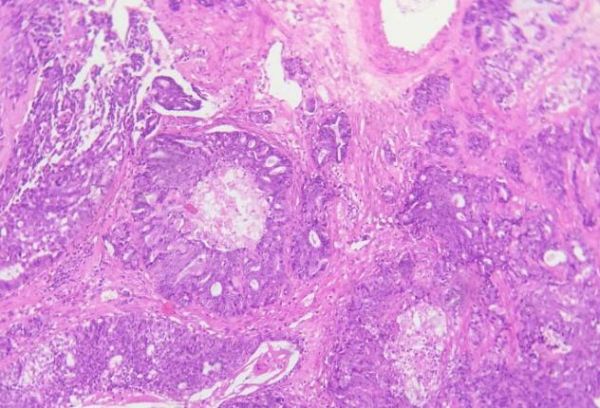

3.6 组织病理学检查:组织病理学切片在40倍显微镜下,乳腺组织正常结构消失,导管上皮增生,肿瘤细胞呈条索状或片状增生,周围结缔组织结构被破坏,可见到鳞状化生区域(见图6、7)。100倍显微镜下,肿瘤细胞大小不等,核仁浓染,部分细胞可见多核仁有多处中央无细胞区域,由坏死、胶原和玻璃样物质组成(见图8、9)。